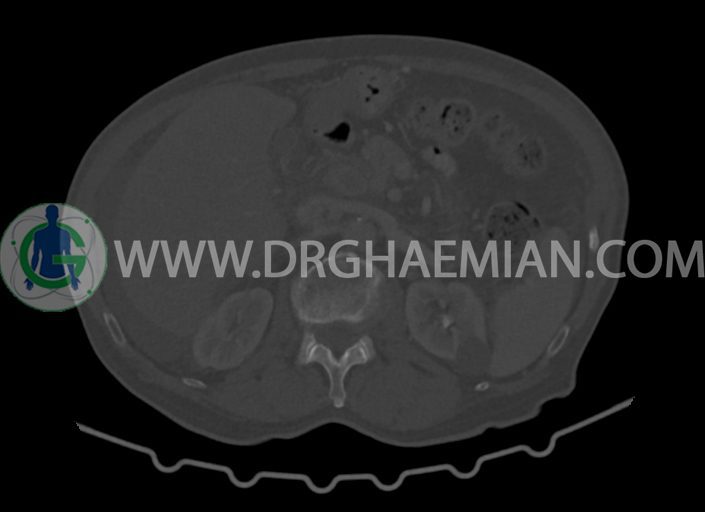

در سی تی اسکن اسپیرال شکم و لگن با کنتراست خوراکی و وریدی (مولتی دیدکتور 16 با مقاطع ظریف و بازسازی های ساژیتال و کرونال) :

-کیست های کورتیکال ساده در هر دو کلیه به بزرگترین قطر 27mm در سمت چپ (بوسنیاک 1)

-کلسیفیکاسیون آئورت شکمی و شاخه های آن

-ناحیه ی مشکوک به افزایش ضخامت جداری در کولون صعودی (نیازمند مطابقت کولونوسکوپی)

-لنف نودهای متعدد بعضا با مرکز نکروزه به شرح زیر رویت شد:

-به بزرگترین SAD=14mm در گاستروهپاتیک

-به SAD=10mm در زنجیره سلیاک

-چند لنف نود به بزرگترین SAD=16mm در محور SMA